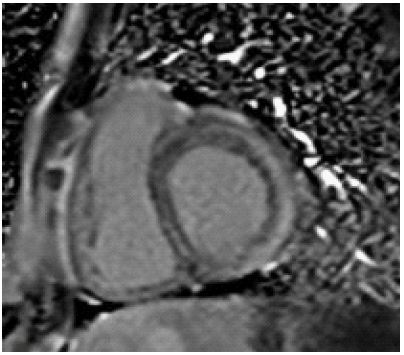

A 33-year-old female with no prior comorbidities presented with a seven-day history of high-grade fever, chills, rigors, dyspnea, and cough with borderline blood pressure requiring inotropes. Preliminary evaluation with ECG revealed sinus tachycardia and a 2D echo revealed global LV hypokinesia and severe Left ventricular dysfunction with LVEF of 30%. Initial laboratory investigations revealed elevated troponin with elevated NT-Pro-BNP suggestive of myocardial injury and acute heart failure, anemia (Hb: 9 g/dL), and elevated TSH (7.8 mIU/L), and mild renal dysfunction. The patient was admitted to the Intensive Care Unit and was treated for Heart Failure. A cardiac MRI was done, and it showed significant mid-myocardial Late Gadolinium Enhancement (LGE) in the LV free wall, sparing the endocardium and epicardium. While mid-myocardial LGE is commonly associated with myocarditis, it can also be seen in other conditions such as sarcoidosis, dilated cardiomyopathy, and Anderson Fabry disease. In this case, the findings were interpreted in conjunction with the clinical presentation, including recent febrile illness, elevated troponin, and rapid LV dysfunction. The imaging met the revised Lake Louise Criteria, supporting a diagnosis of probable myocarditis (Figures 1-3). Patient was started on IV Methylprednisolone 1 g daily for three days and then started on Oral prednisolone 1 mg/kg/day. Four days into her illness, she experienced two syncopal episodes and was found to have bradycardia with a heart rate of 30/min. An ECG revealed a complete heart block (Figure 4) with a wide-complex escape rhythm, and rising troponin levels indicated myocardial injury. A transvenous temporary pacemaker was placed, stabilizing her initially. A formal Transthoracic Echocardiogram (TTE) was performed after temporary pacemaker placement, which revealed the same moderate to severe LV dysfunction and no additional complications. Sarcoidosis was considered due to mildly elevated ACE levels (61 U/L), but further testing, including CT chest, EBUS, and node biopsy, was not feasible due to the patient’s rapid deterioration. Giant cell myocarditis, though rare in young patients, was also considered, given the aggressive course and refractory ventricular arrhythmias. A comprehensive evaluation could not be conducted due to the rapid progression of the disease. However, viral myocarditis remained the most likely etiology based on clinical presentation, negative H1N1 swab, and absence of autoimmune markers (ANA: 1:40, dsDNA < 30 IU/mL) (Table 1). After TPI, she developed slow ventricular tachycardia (130/min) (Figure 5), which persisted despite multiple attempts at overdrive pacing. Amiodarone was initiated (150 mg IV bolus, followed by 1 mg/min for 6 hours, then 0.5 mg/min for 18 hours), but VT remained refractory. Lidocaine (1.5 mg/kg IV bolus, followed by 1 mg/min infusion) was added, but the arrhythmia remained refractory. Overdrive pacing was attempted but was discontinued after the onset of Polymorphic Ventricular Tachycardia (PMVT). Given the fulminant nature of myocarditis, catheter ablation was not attempted, as the arrhythmogenic substrate was likely diffuse rather than focal, reducing the likelihood of procedural success. The patient continued to deteriorate into refractory cardiogenic shock despite maximal inotropic and antiarrhythmic therapy. She experienced cardiac arrest and could not be resuscitated. Referral for mechanical circulatory support (ECMO) was considered, but stabilization for transfer was not possible given the rapid decline. Post-mortem biopsy was not performed due to lack of consent.